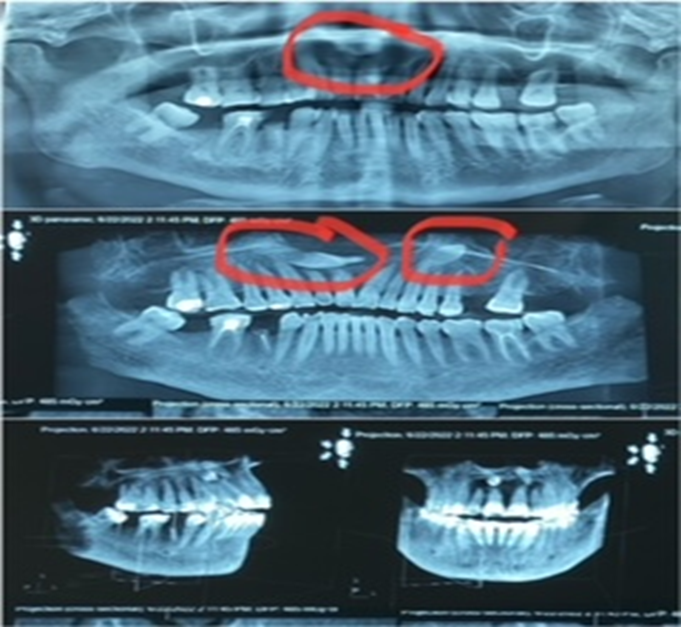

- Trường hợp 2: Bệnh nhân nữ, 75 tuổi đến khám với lý do khối sưng vùng vòm khẩu cái cách đây hơn 01 năm, nay kích thước lớn dần nên vào viện. Thăm khám lâm sàng thấy vòm khẩu cái tương ứng vùng răng 11, 12 có khối sưng, mật độ mềm, có dấu bóng nhựa, giới hạn không rõ, ấn đau nhức. Nướu quanh răng 11, 12 viêm đỏ. Bệnh nhân được chụp phim XQ răng toàn cảnh thường qui để kiểm tra thấy hình ảnh thấu quang rộng từ vùng chân răng 13 đến răng 21. Bệnh nhân được chụp tiếp Cone Beam CT, qua các lớp cắt đã thấy rõ hình ảnh có có răng mọc ngầm lệch hoàn toàn trong xương vùng chân răng 11, 12, 13 và 22, hình ảnh thấu quang rộng từ vùng chân răng 13 đến răng 21, kích thước khoảng 3x3cm. Bác sỹ điều trị lập kế hoạch cụ thể phẫu thuật nạo nang lấy bỏ răng ngầm.